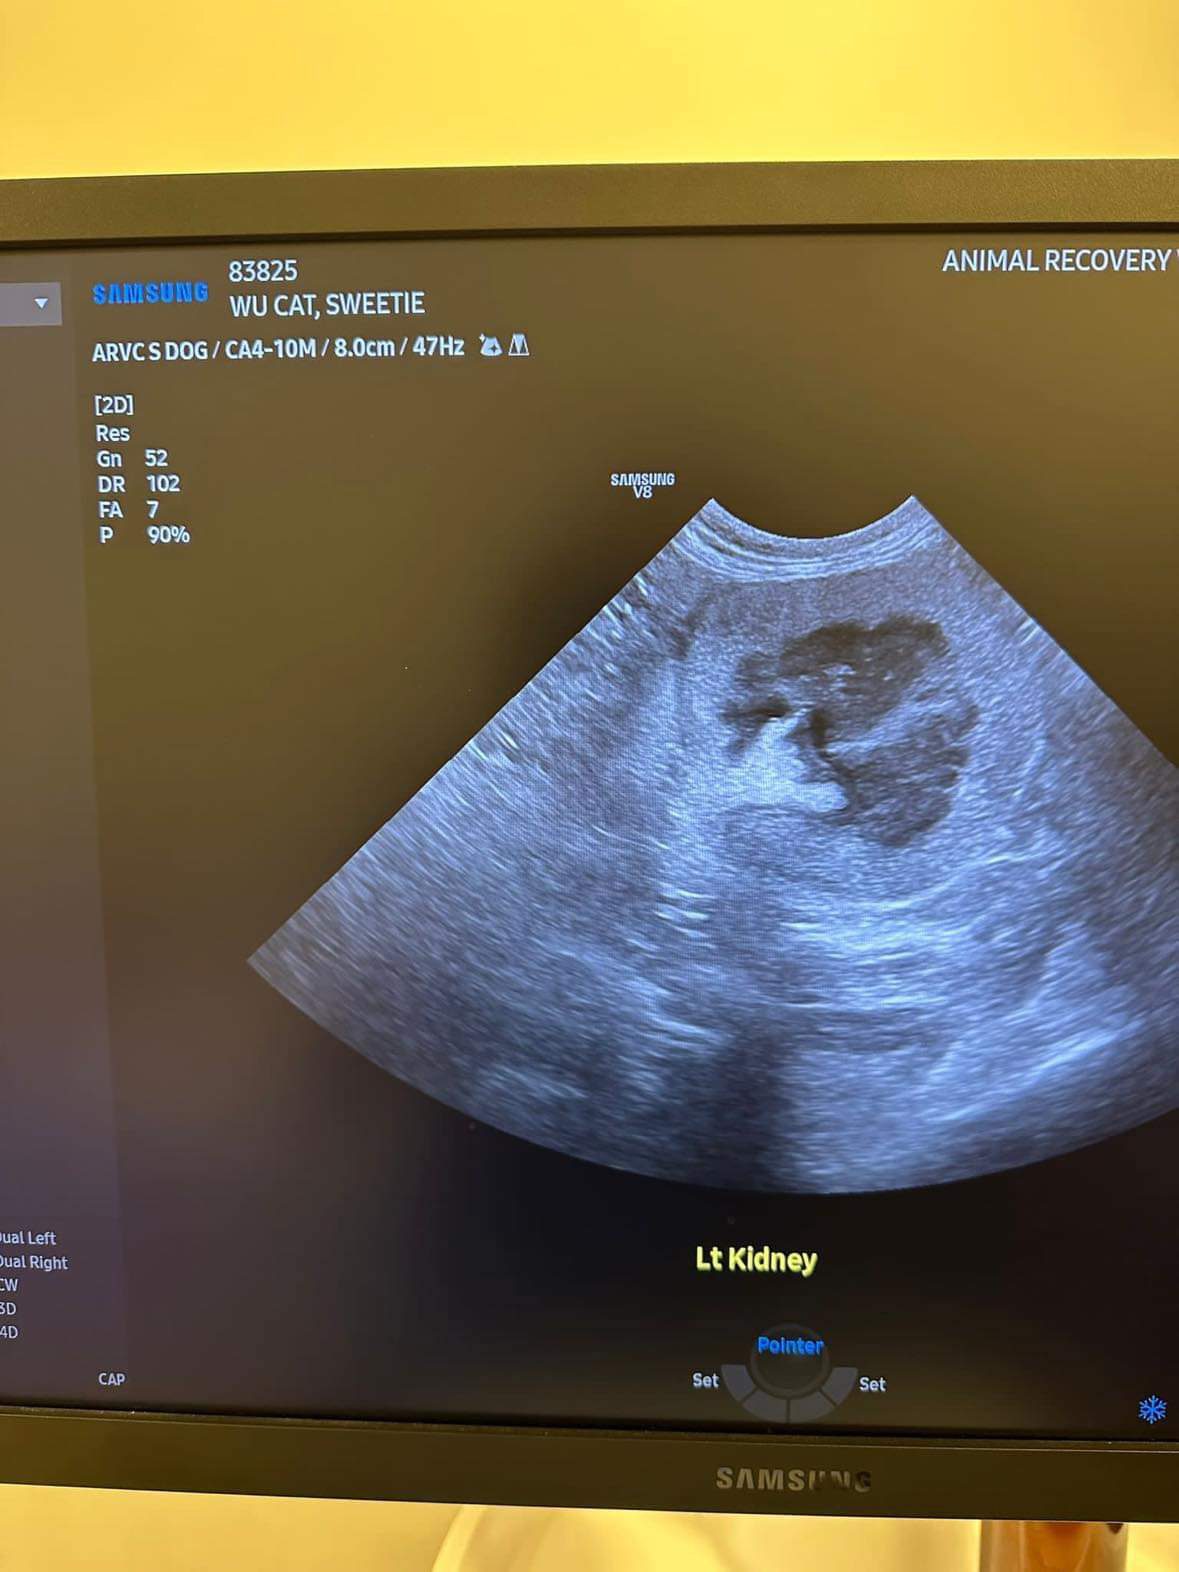

11.28am: Scarlett bring her into the room for abdominal u/s.

U/s done and basically not much use to me, liver got issue, kidneys got some fatty deposits which is diabetic, so insulin correct. Gall bladder got some obstruction so just start urofalk. All in must put o tube. Dr Daniel do it.

her left kidney 8.0cm, right 7.0cm also double the normal size

Dr ym scan sweeties, dr flo not involve, both got free fluid ard the kidneys, left kidney is extremely abnormal, right kidney abnormal.